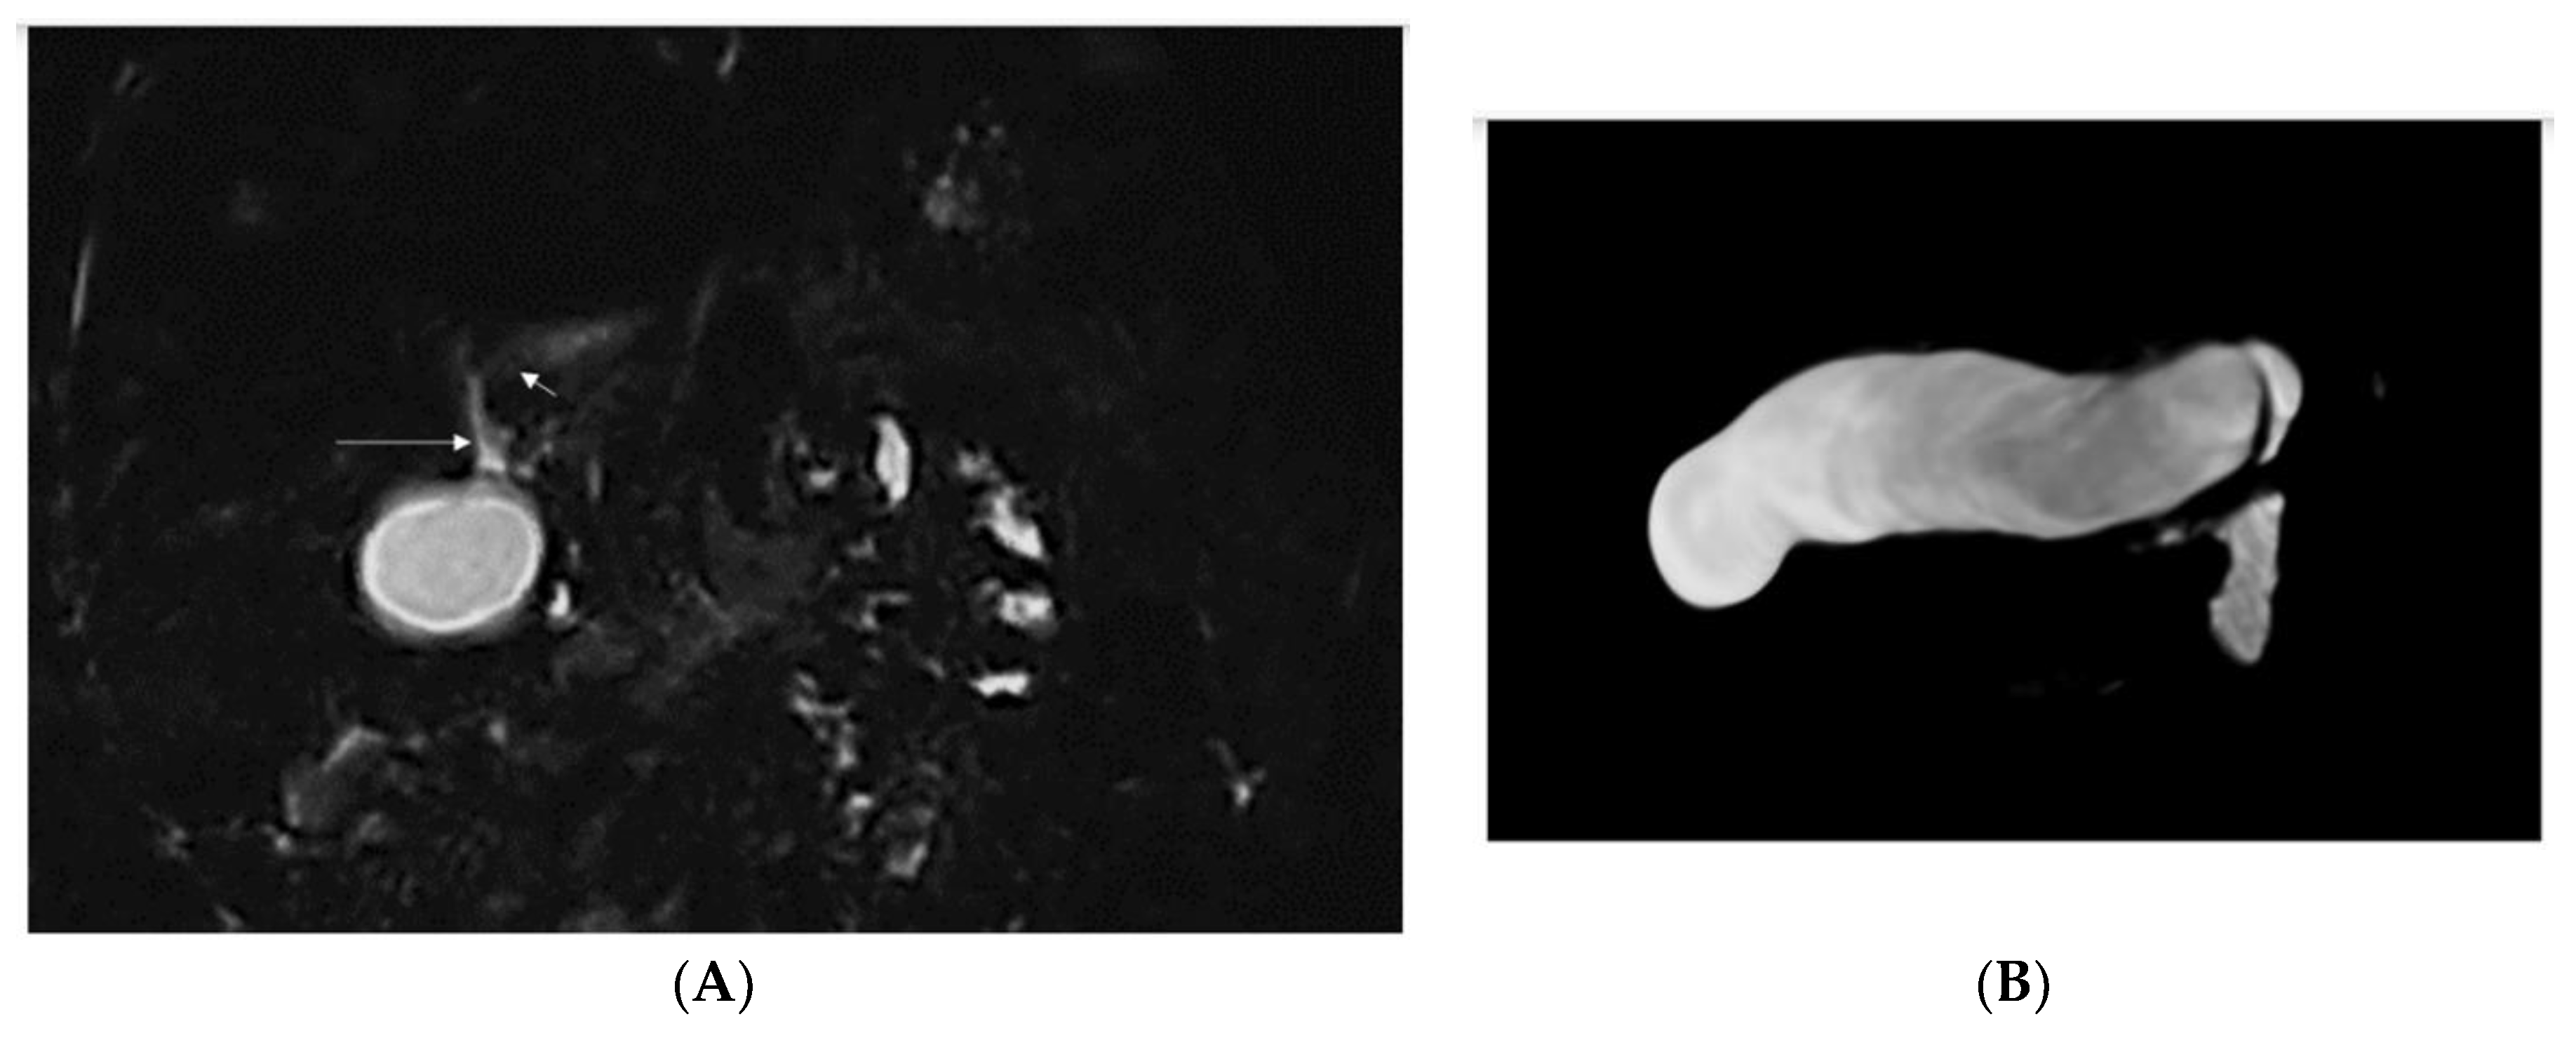

| 2/F Sister of Pt 1 | Caucasian | 2nd day of life | Jaundice, acholic stools, elevated GGT | Yes (8 mo) See Figure 1 | No liver biopsy | No | 9 m | right vesico-ureteral reflux II degree, persistent urachus | c.[123_124del];[256del], p.(Ser42Glnfs*72)/ p.(Tyr86Thrfs*17) compound heterozygote |